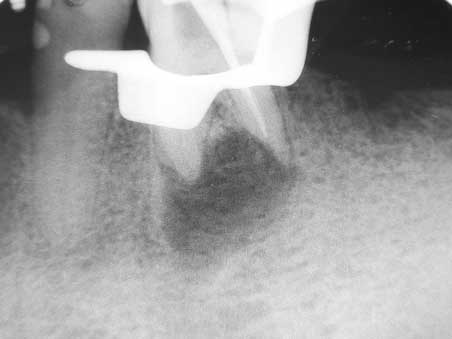

Apikale Aufhellung 001 Bild 2

Veröffentlicht 10. Februar 2009 am 452 × 339 in Apikale Aufhellung (1)